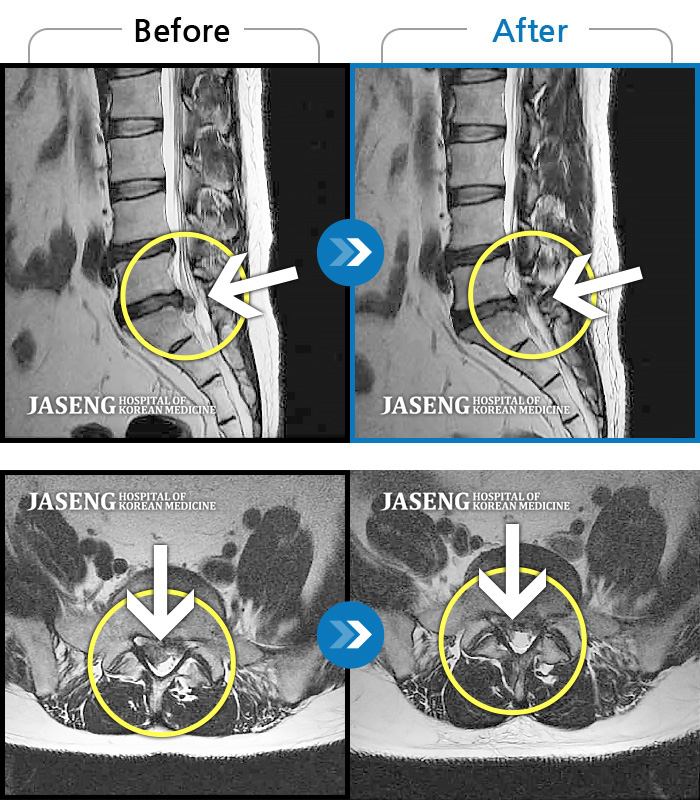

허리디스크

잠실 · 한상욱 원장

허리가 많이 아프고 왼쪽 다리가 저려 움직이기가 힘들다.

촬영시기

2022.01.19 ~ 2022.11.14

2022.12.02